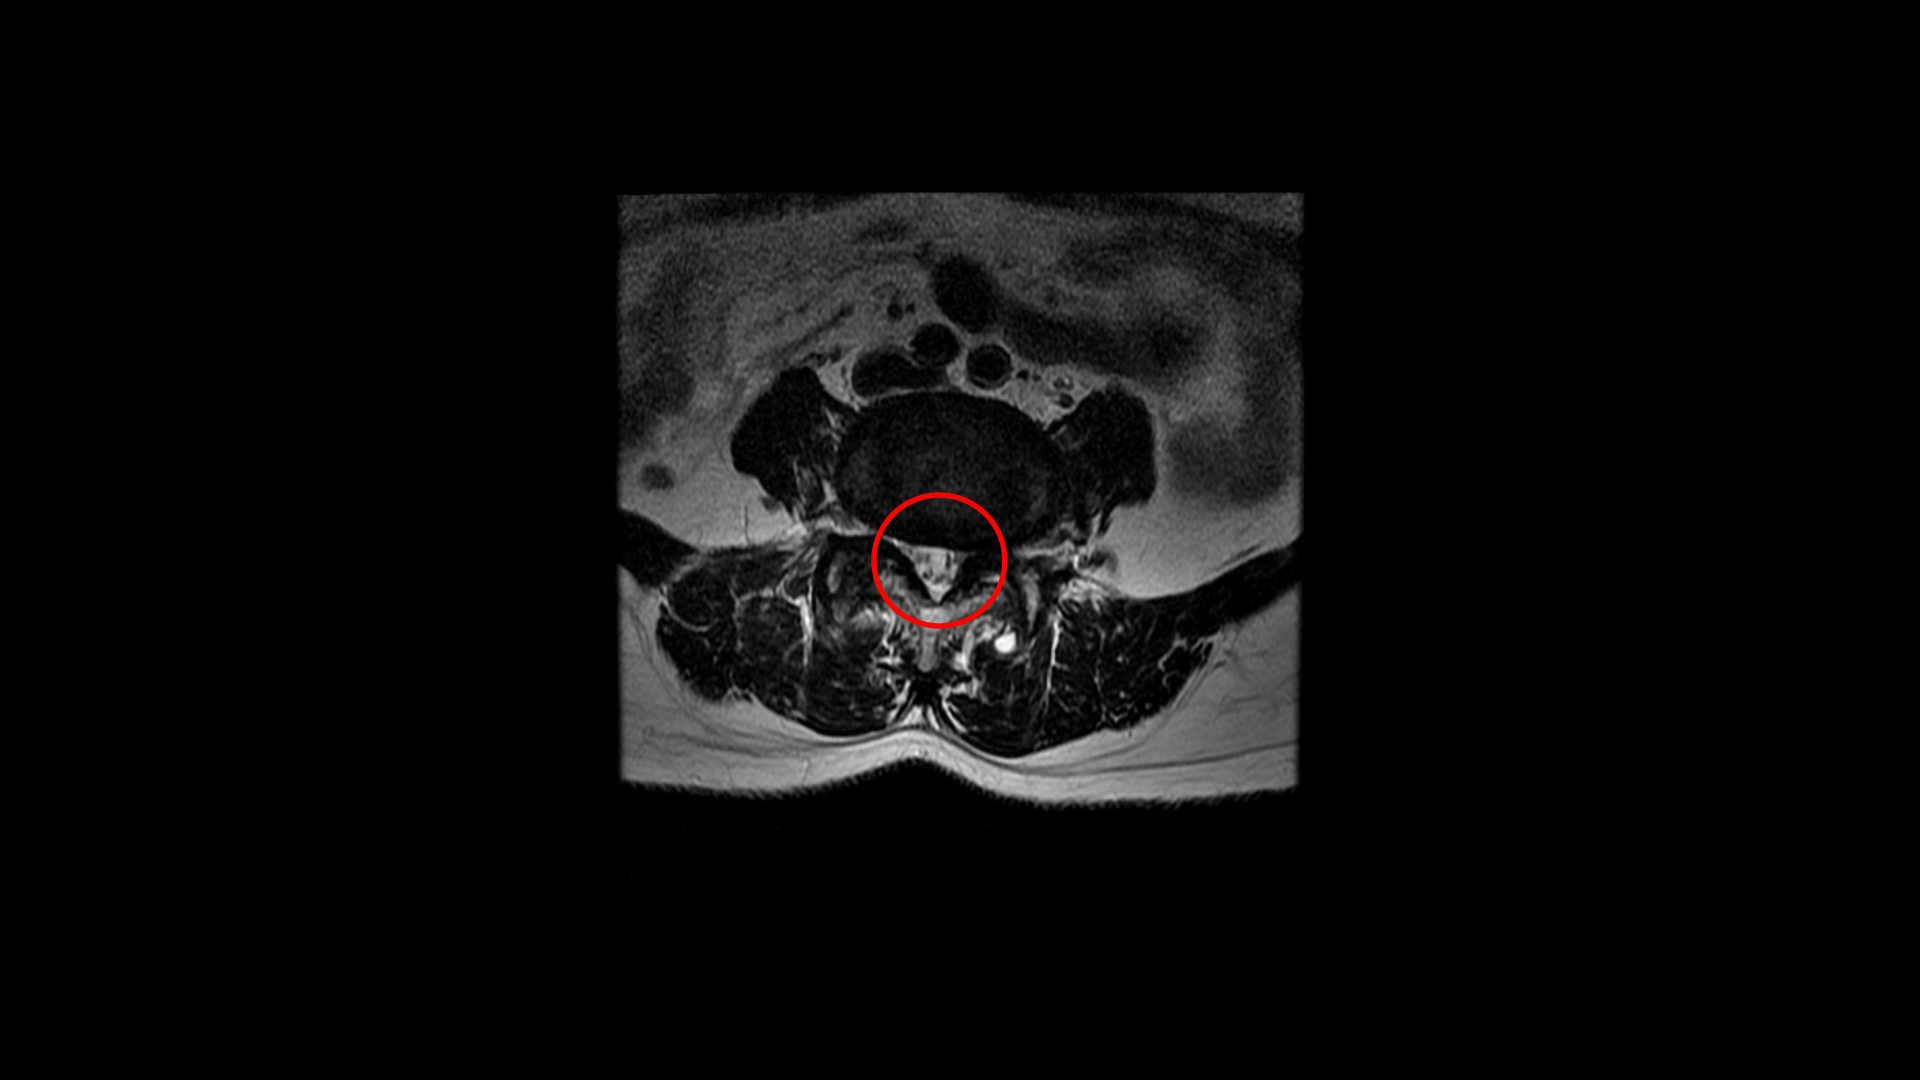

우선 이 환자분의 MRI를 함께 보겠습니다. 이 환자분의 척추에는 3번 4번과 4번 5번에 각각 1단계의 전방전위증이 있습니다.

3번 4번에는 왼쪽으로 디스크 탈출이 있고

중심성 협착도 있습니다.

그리고 4번 5번에도 왼쪽으로 퇴행성디스크와 후관절의 퇴행으로 신경 가지가 나가는 구멍이 좁아져 있습니다.

그리고 중심성 협착도 있습니다.

그런데 이 환자분의 제일 불편한 증상은 왼쪽이 아니고 오른쪽 엉치와 다리 증상입니다. 이분 오른쪽 신경 구멍들을 보면 전부 다 넓게 잘 열려 있습니다.

엉치와 다리 방사통을 일으킬만한 특별한 신경 눌림이 보이지 않는 것입니다. 그럼에도 불구하고 여러 마디의 전방전위증과 척추관 협착 그리고 디스크 탈출이 있으니까 그것을 원인으로 보고 신경 주사도 맞고 시술도 받으셨습니다. 그러나 별 효과는 없었습니다. 그리고 대학병원에서도 결국은 수술밖에 방법이 없다고 수술을 권유하였습니다.